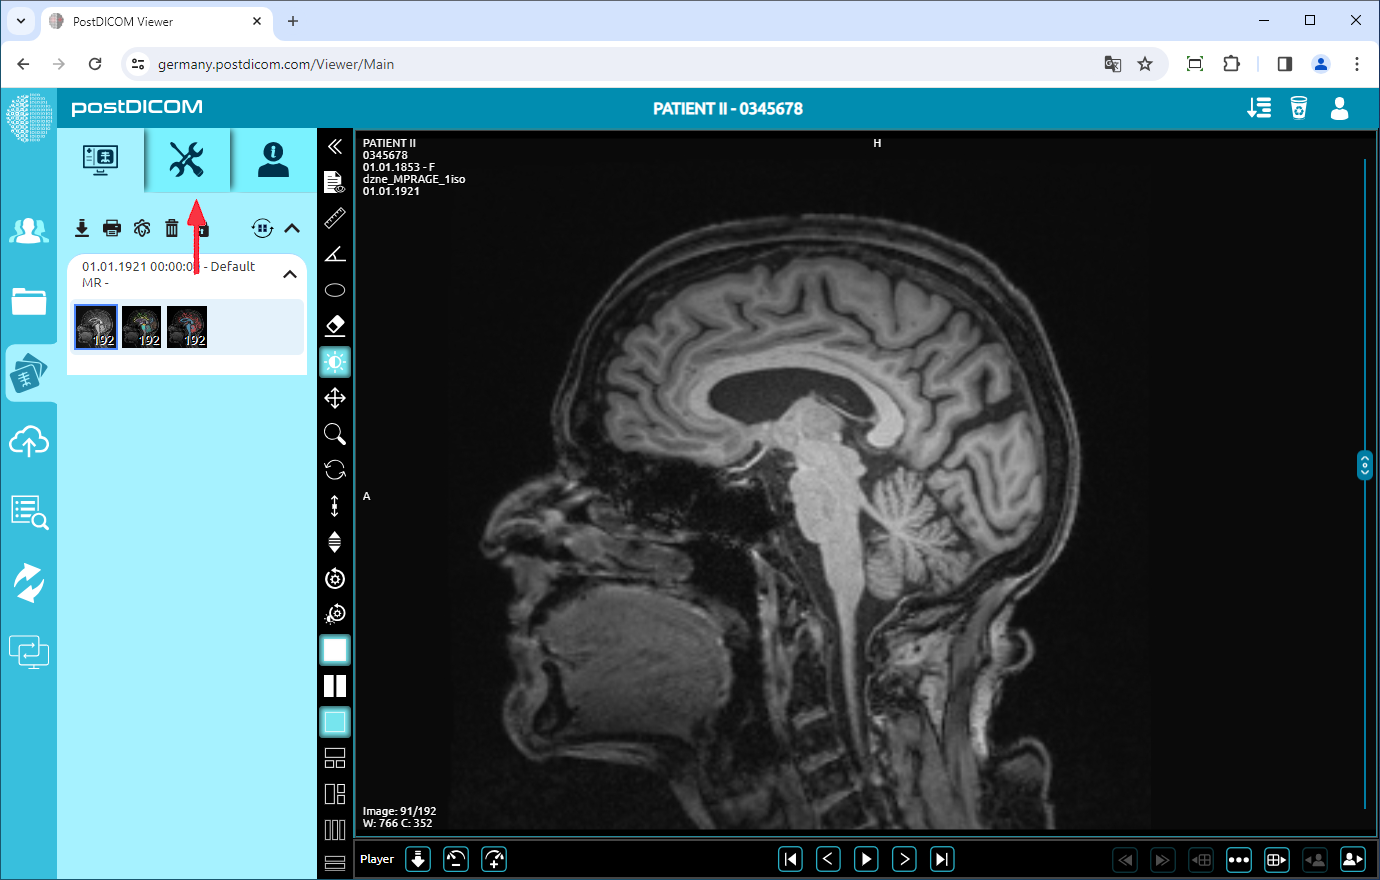

On the “Patient Search” page, all patient orders in your account will be shown. Double-click on the order you want to view the images. The “View” page will be opened. Click on the “Tools” icon on the upper left side of the page.

After you have clicked, the tools section will be displayed. In the “Annotations” field, click on the “Ruler” icon on the upper left side of the section.